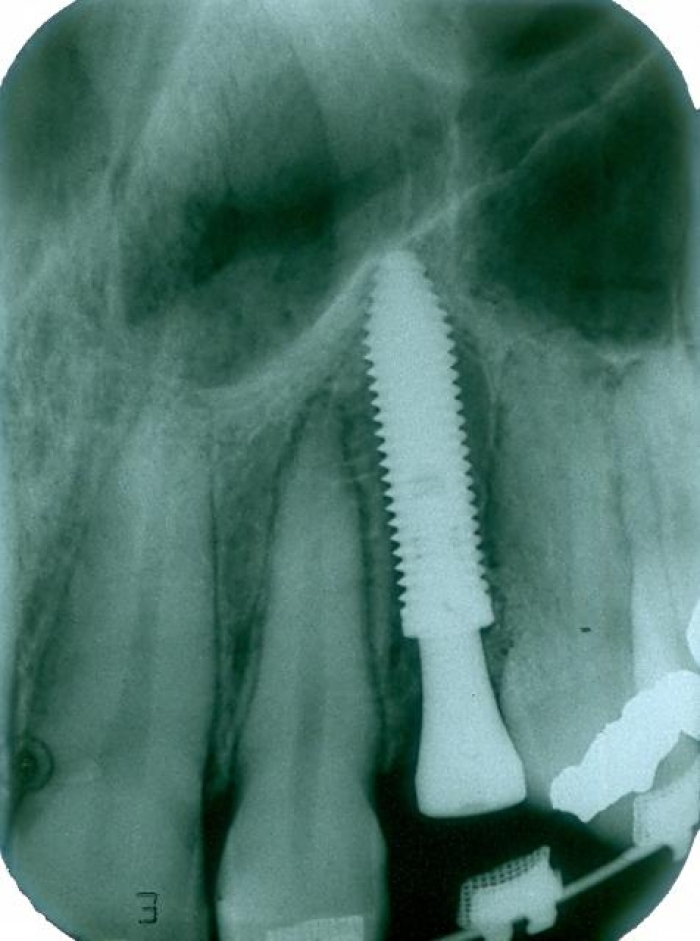

Raio X após a extração e implante imediato